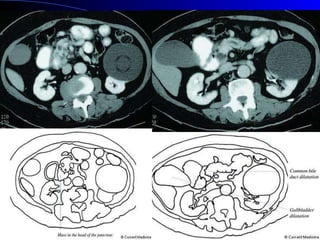

Presentación clínica 60 % se presentan en la cabeza del páncreas Sintomatología por efecto de masa más que por disfunción exo/endonina Dependen del tamaño y localización Neoplasias páncreas. Rosesch Dietlen pag 545-560

Presentación clínica 60% se presentan en la cabeza del páncreas Sintomatología por efecto de masa más que por disfunción exo/endonina Dependen del tamaño y localización Neoplasias páncreas. Rosesch Dietlen pag 545-560

Diagnóstico CLÍNICO: Avanzadoe incurable. LABORATORIO: Anemia, desnutrición, obstrucción biliar, hiperamilasemia. US: Sensibilidad: 80%, especificidad: 75%. (>3 cm). Ganglios, dilatación VB. TAC: Estudio inicial de elección. CPRE: Obstrucción del Wirsung. Dr. Nogueira de Rojas

Estudios de imagenUSG abdominal TAC helicoidal dinámica en tres fases: estándar de oro para diagnóstico y valorar resecabilidad CPRE RMN TEP Neoplasias páncreas. Rosesch Dietlen pag 545-560

• #60 El USG abdominal debe ser el primer estudio en pacientes con ictericia Una CPRE para diferenciar ictericia obstructiva en pacientes sin tumoración demostrable por tomografía, eo en pacientes